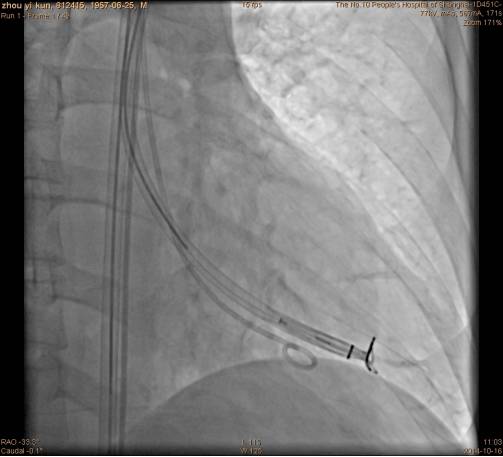

沿指引导管置入Parachute,左室造影与心超检查位置。

手术过程隔离装置的脚到位: